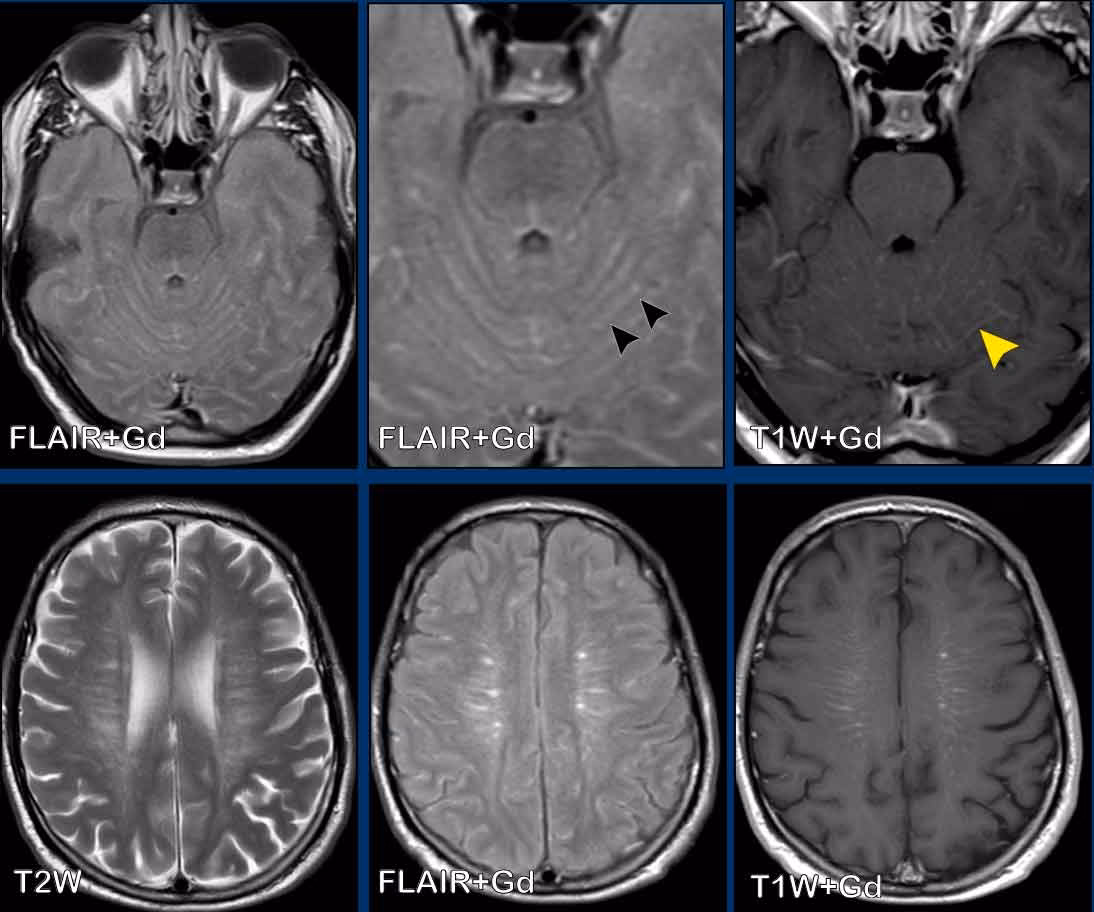

Ved MR-scanning af meningitis anvendes ofte et kontraststof (gadolinium), som sprøjtes ind i en blodåre. Kontraststoffet fremhæver områder med betændelse, hvor blod-hjerne-barrieren er brudt. Der findes to overordnede mønstre for meningeal kontrastopladning:

- Leptomeningeal (Pia-subarachnoid) opladning: En tynd, fin opladning, der følger hjernens overflade ind i furerne (sulci) og cisternerne. Dette mønster er mere typisk for infektiøse årsager, herunder viral meningitis.

1. Leptomeningeal Kontrastopladning

Som ved de fleste virale meningitider er det mest almindelige fund ved VZV meningitis en leptomeningeal kontrastopladning. Dette ses som fine, slyngede linjer af kontrast, der følger hjernens og rygmarvens konturer. Betændelsen i de indre hjernehinder (pia og arachnoid mater) er det, der visualiseres her. Selvom dette fund ikke er specifikt for VZV, er det et stærkt tegn på en infektiøs eller inflammatorisk proces i subaraknoidalrummet.